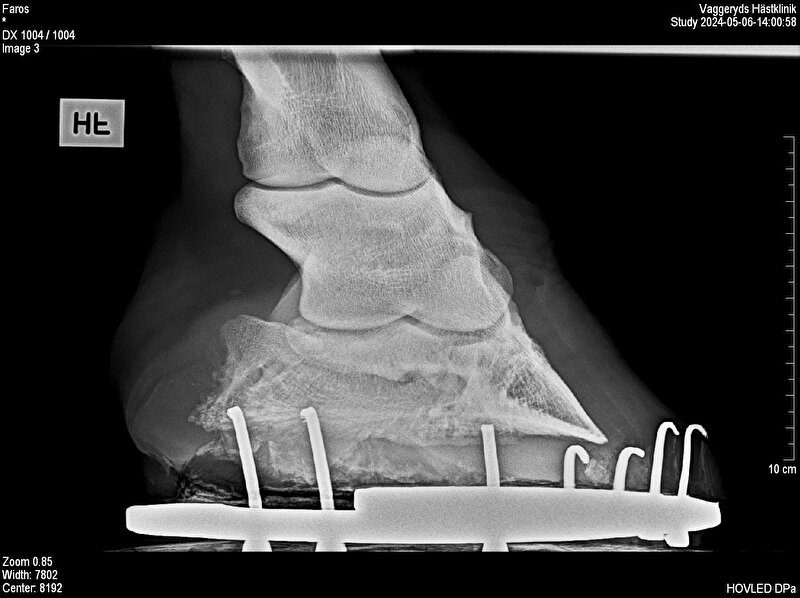

Twee weken later weer wezen te keuren, ik ben naar een groter stuk asfalt gegaan om te longeren en daar liep ie goed. Filmpjes zijn doorgestuurd naar twee klinieken en beide vonden hem goed, dus vol goede moed die kant op. Maar, sure hij was veel beter maar nogsteeds niet goed. Ene voet uitverdoofd waar ie mee markeerde, toen was ie kreupel op zn andere voet. Foto’s laten maken en dat zijn dus deze. De dierenarts ziet er wel iets op, maar vind t niet noemenswaardig dat t daarvan zou komen, ze blijft volhouden dat het uit zn ijzers komt, dat ie te krap beslagen is. Heb dan ook een afspraak staan bij hun hoefsmid maar die kan pas de 30e.

Zouden jullie eens willen meekijken en vertellen wat jullie zien?

Rechts voor